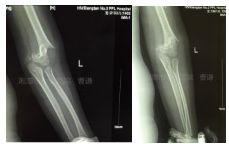

GartlandⅢ型肱骨髁上骨折患者,患肢畸形、肿胀明显。肘前方可见皱褶,典型的难复型肱骨髁上骨折。

外院拍片情况如下: